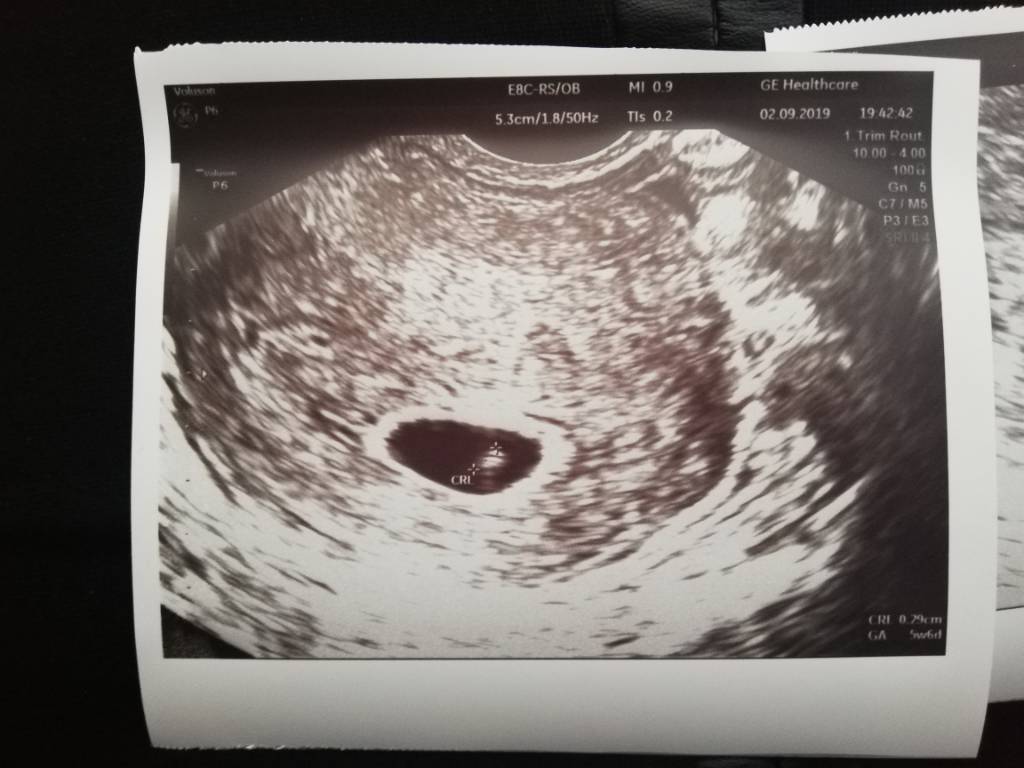

Jest kropek i jest serducho [emoji3590]

Wg Om 6t3d wg USG 5t6d ale to nieznacząca różnica.

Z tego wszystkiego nie zapytałam jakie jest tętno [emoji58]Zobacz załącznik 1017577